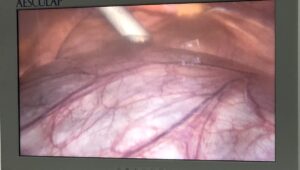

Trung tâm Y tế huyện Vân Đồn triển khai điều trị bệnh trĩ không cần phẫu thuật bằng thủ thuật Tiêm xơ búi trĩ

Sau khi tiếp nhận chuyển giao kỹ thuật từ tuyến trên về phương pháp tiêm ...